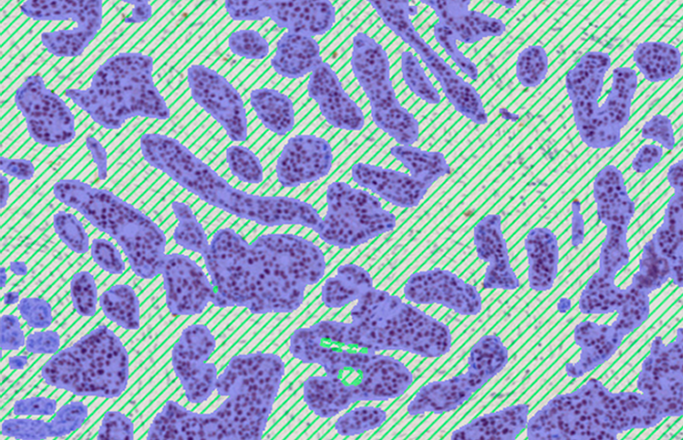

Available for brightfield (H&E, IHC), immunofluorescence (IF, DAPI), imaging mass cytometry (IMC).

Intuitively explore even complex tissue data

Easy-to-use AI deep learning is standard in all of our research applications.

With Discovery, anyone with an understanding of tissue morphology can train an AI deep learning APP to get accurate and reproducible results.

All you need is your expert biological knowledge.

Apply your tissue expertise and annotate the structures you want to identify. Our intuitive drawing tool allows for quick and seamless annotation.

The software will characterize the best features to robustly detect your structures even across heterogeneous tissues.